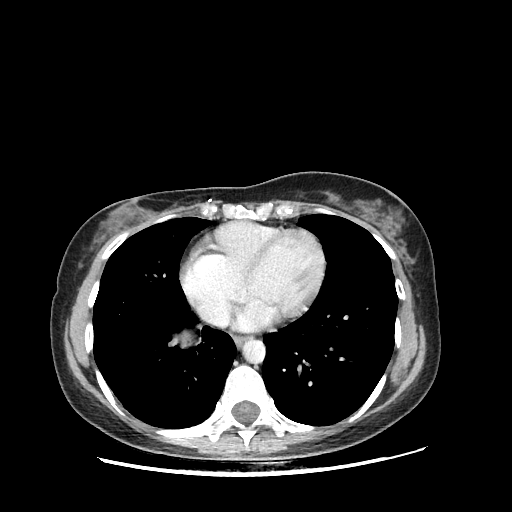

Generated VENOUS CT scan (A→B translation)

Full window (WL 1023.5, WW 4095 β†’ Low βˆ’1024, High +3071)

Actual HU range: [-1024.0, 892.4]